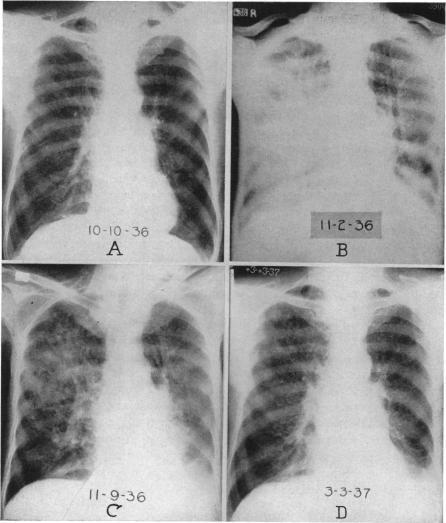

INTRATRACHEAL SUCTION IN THE MANAGEMENT OF POSTOPERATIVE PULMONARY COMPLICATIONS.

Ann Surg. 1938 Feb;107(2):218-28. doi: 10.1097/00000658-193802000-00004.